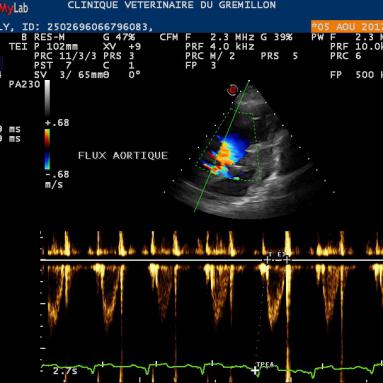

Les modes Doppler servent à visualiser et à mesurer les vitesses des flux de sang. Ils sont au nombre de trois:

• Le Doppler continu: ce mode est le meilleur moyen pour mesurer la vitesse d'un flux sanguin orienté dans le même sens qu'une ligne que l'on va diposer et orienté à notre guise. Il est indispensable de placer cette ligne avec la même orientation que le flux de sang, une deviation de quelques degrés sous estimera la vitesse réelle du flux

Le rapport du temps de pré-ejection systolique sur le temps d'éjection systolique: DTE/TE <0,3

DTE: temps entre le Q de l'ECG et le debut du flux aortique

TE: temps d'éjection aortique